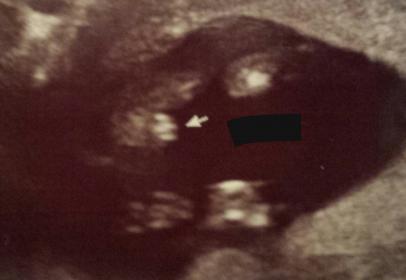

Tech was pretty certain on gender. Want to see how your guesses match up.

That's boy bits!!!!!!

Thanks. Let me add that this is a 14+3 shot

I'll go with girl, at 14+3 I would think the little doodle would stick out a bit more?

Maybe girl?